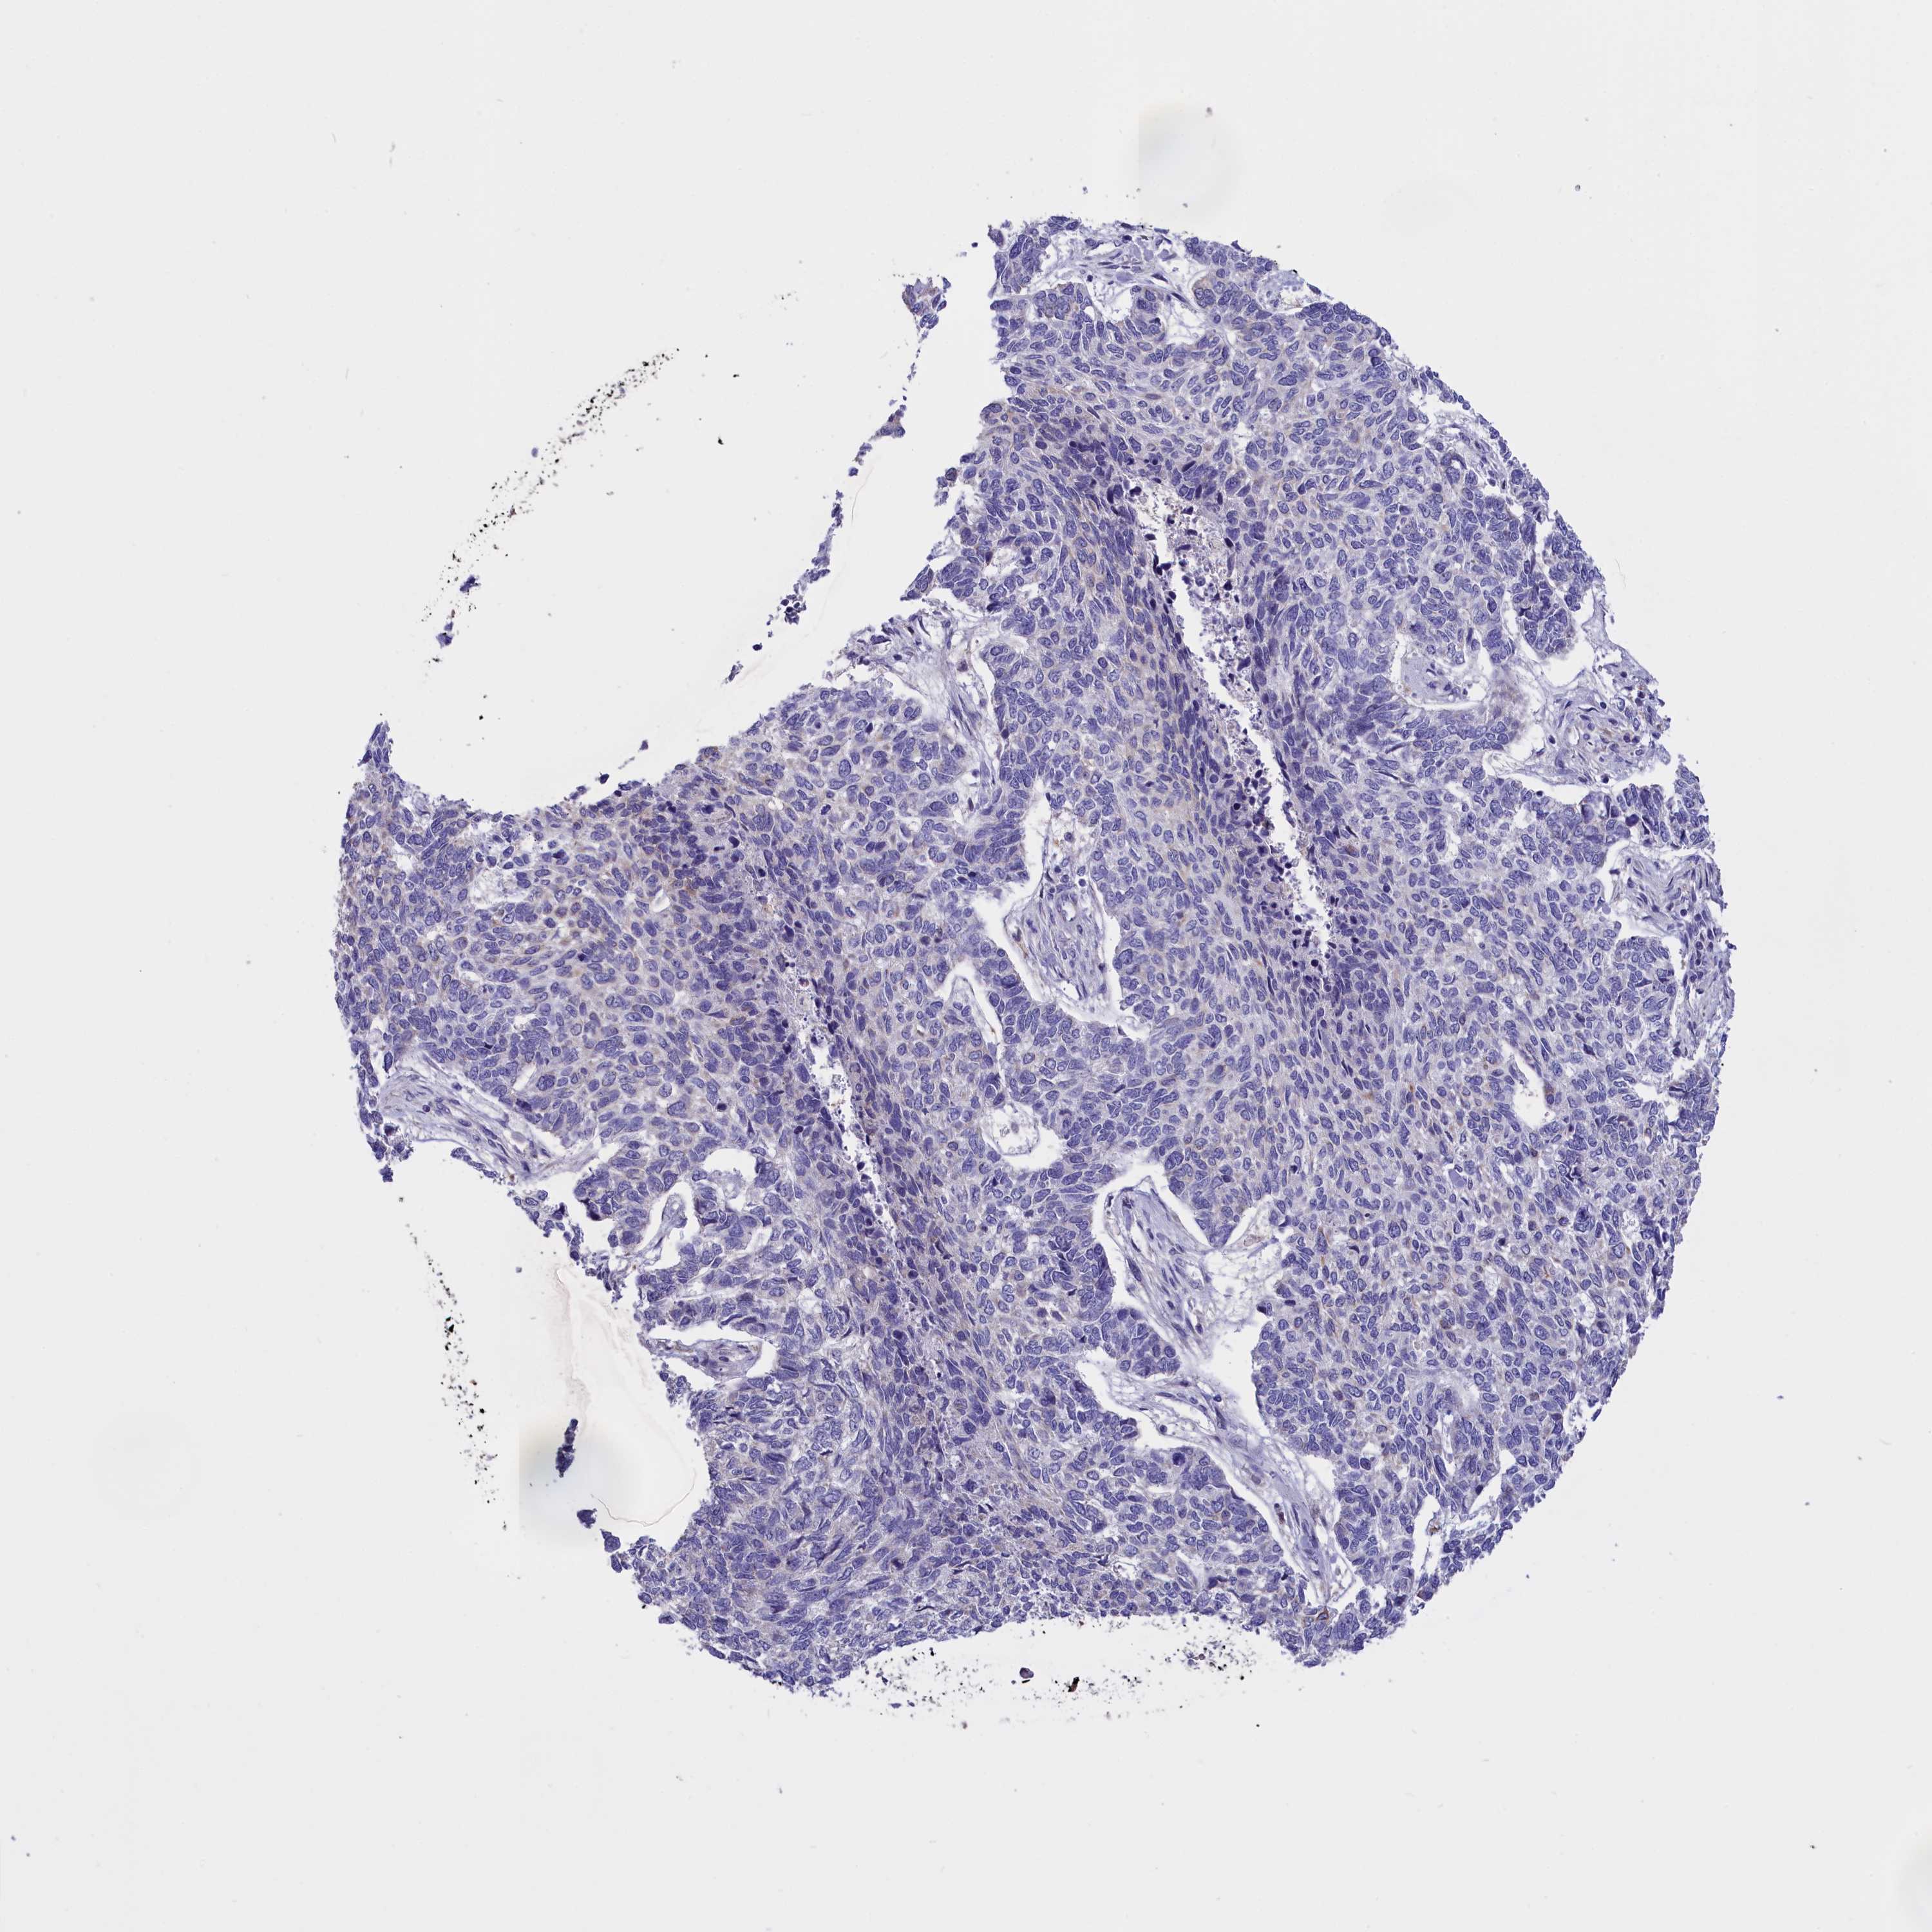

CANCER SKIN CANCER Show tissue menu

Basal cell and squamous cell cancer

SKIN CANCER - Protein expressioni

A mouse-over function shows sample information and annotation data. Click on an image to view it in a full screen mode. Samples can be filtered based on level of antibody staining by selecting one or several of the following categories: high, medium, low and not detected. The assay and annotation is described here.

Each image is clickable and will lead to virtual microscopy that enables deeper exploration of all samples and also displays staining intensity scores, fraction scores and subcellular localization as well as patient and tissue information for each sample.

Antibody HPA046754

Squamous cell carcinoma, NOS

Squamous cell carcinoma, metastatic, NOS

Squamous cell carcinoma in situ, NOS